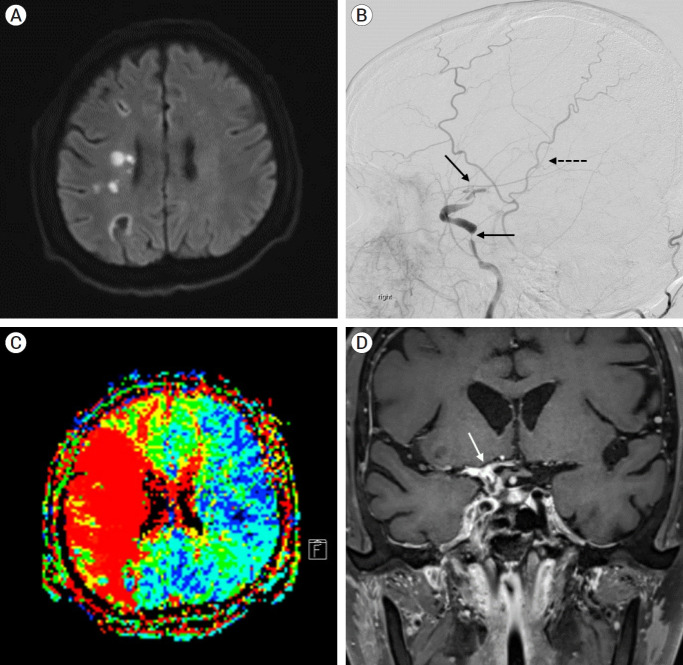

中枢神经系统(CNS)曲霉病是一种危及生命的感染,主要影响免疫功能低下患者,并可能通过血管侵入导致严重的脑梗死。然而,关于曲霉病诱发的脑梗死的治疗选择的数据有限,特别是手术治疗,如颞浅动脉(STA)-大脑中动脉(MCA)搭桥手术。在此,我们报告一个59岁男性右眼进行性上睑下垂的脑梗死病例。具体来说,他有同侧MCA狭窄,起源于侵袭性曲霉菌病引起的鼻窦炎。3个月后,患者因脑梗死恶化和颈内动脉完全闭塞再次入院。保守治疗未能改善脑灌注,导致神经功能逐渐衰退。因此,行STA-MCA搭桥以稳定患者。术后影像学显示通畅的旁路移植术和增强的脑灌注。虽然患者经历了持续的左侧偏瘫,但他的整体神经系统状况保持稳定1年,格拉斯哥昏迷评分为15分。对于曲霉菌病引起的血管炎导致脑梗死继发于ICA全闭塞的患者,STA-MCA旁路治疗应被视为一种潜在的治疗选择。

Central nervous system (CNS) aspergillosis is a life-threatening infection primarily affecting immunocompromised patients and may lead to severe cerebral infarction through vascular invasion. However, there is limited data on the treatment options for aspergillosis-induced cerebral infarction especially surgical treatments such as superficial temporal artery (STA)-middle cerebral artery (MCA) bypass surgery. Herein, we present a case of cerebral infarction in a 59-year-old male with progressive right eye ptosis. Specifically, he had ipsilateral MCA stenosis originating from paranasal sinusitis due to invasive aspergillosis. After 3 months, the patient was readmitted due to worsening cerebral infarction and complete internal carotid artery (ICA) occlusion. Conservative treatment failed to improve cerebral perfusion, leading to gradual neurological decline. Consequently, STA-MCA bypass was performed to stabilise the patient. Postoperative imaging revealed a patent bypass graft and an enhanced cerebral perfusion. Although the patient experienced persistent left-sided hemiparesis, his overall neurological condition remained stable for 1 year, with a Glasgow Coma Scale score of 15. STA-MCA bypass should be considered a potential treatment option for patients with aspergillosis-induced vasculitis resulting in cerebral infarction secondary to total ICA occlusion.